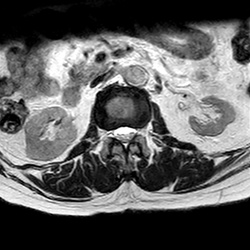

MRI_eAX_T2W_Thoracal_702

42 photos